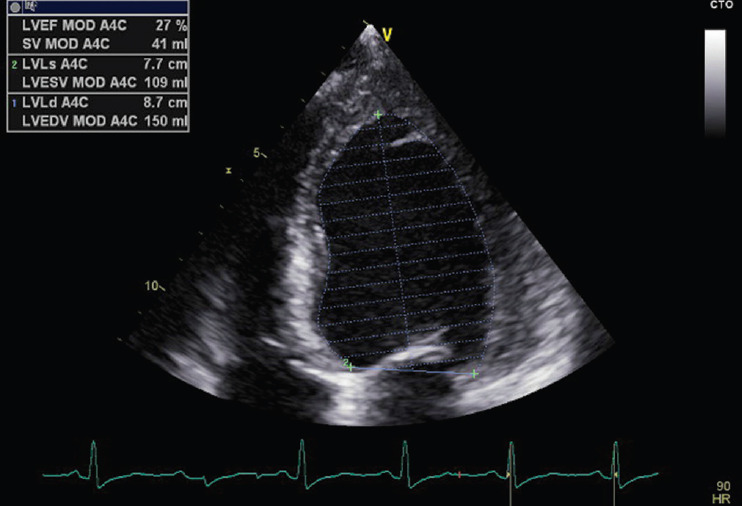

Peripartum cardiomyopathy (PPCM) is a specific form of cardiomyopathy that manifests toward the end of pregnancy or within 5 months postpartum, characterized by a decrease in cardiac output due to impaired myocardial function. This condition has a multifactorial origin, influenced by genetic predispositions, inflammatory processes, autoimmunity, hormonal variations, and nutritional deficiencies. Prognosis varies among patients: while some recover completely within 6 months, others may develop chronic cardiac dysfunction requiring long-term treatment. Vericiguat, a soluble guanylate cyclase stimulator, has shown promising results in the treatment of heart failure with reduced ejection fraction. This drug works by enhancing the nitric oxide signaling pathway, promoting vasodilation, and improving myocardial function. Although the use of vericiguat in PPCM is not yet fully documented, its potential benefits suggest that it may represent a valid therapeutic option when standard therapies are insufficient for symptom control. We present the case of a 32-year-old woman with PPCM, initially undiagnosed, who developed severe symptoms of dyspnea, orthopnea, and peripheral edema postpartum. These symptoms were accompanied by a significant reduction in left ventricular ejection fraction. Following a suboptimal response to standard heart failure therapy, vericiguat was incorporated into her treatment regimen. In subsequent outpatient follow-ups, the patient's symptoms progressively improved, and left ventricular systolic function markedly increased. The patient became asymptomatic and was able to resume her normal daily activities. While this case suggests that vericiguat could be an effective adjunctive treatment for PPCM, it remains unclear whether these improvements were directly attributable to vericiguat or could have occurred with continued standard therapy alone. Further studies are needed to define the role of vericiguat in this condition.

Abstract Image